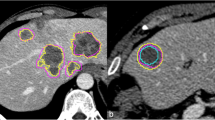

For semi-automated evaluation using the software Syngo Oncology (Siemens Medical Solutions, Forchheim, Germany), patient data were transferred to the software through the network. Semi-automated measurements are started with a directed mouse click into the lesion in axial, coronal or sagittal view. Software results are presented graphically to the user. Manual editing would be possible but was not allowed in our study. In keeping with the manual measurements, semi-automated measurements were named as follows (Fig. 2):

- O1 :

-

Longest axial diameter

- O2 :

-

Longest diameter perpendicular to O1 in the same image

- O3 :

-

Product of O1 and O2 (O1 × O2)

Screenshot applying the Oncology software tool to the same patient represented in Fig. 1